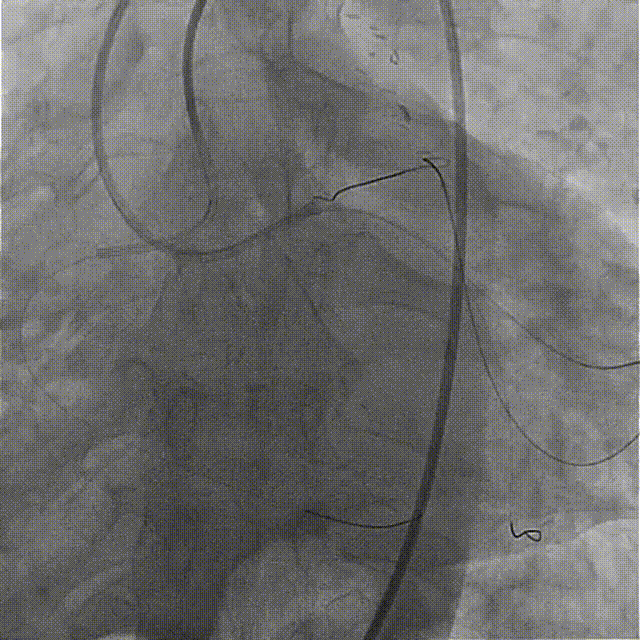

置7F UBS 3.75、6F JR 4.0指引导管至左右冠开口,分别送入Marvel导丝至LCX远段、RCA远端加强支撑,行双侧造影。

在微导管支撑下,Sion导丝无法经OM1心外膜侧枝逆向至LAD远段,改送Fielder XT-R导丝逆向至LAD远段。

HighTrack微导管跟进至闭塞病变远端,正向工作导丝做指引,应用Fielder XT-A导丝逆向通过闭塞段至LM内,反复尝试调整导丝未能进入正向指引导管。